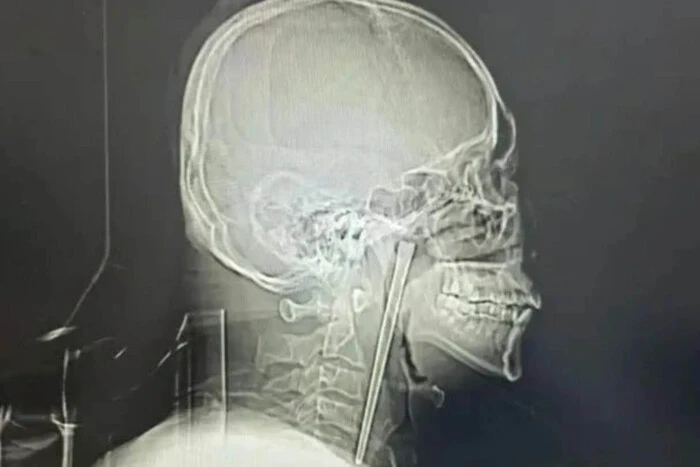

У Китаї чоловіку, на прізвище Ван провели незвичну операцію. З його горла видалили металеву палицю, з якою він жив протягом восьми років. Про це розповідає «Главком» із посиланням на SCMP.

Ван проковтнув металеву палицю разом із їжею ще вісім років тому. Однак свого часу через побоювання він відмовився від того, щоб її видалити. Роками йому доводилося терпіти дискомфорт у горлі.

Медики під час обстеження виявили у піднебінні пацієнта металевий предмет. Та попри сторонній предмет у тілі, який залишився там роками, голосові зв’язки та тканини навколо нього не постраждали.

Врешті лікарі провели малоінвазивну операцію через рот, аби не робити розріз шиї пацієнт. У результаті фахівці видалили металеву палицю розміром 12 см. Операція пройшла успішно та без ускладнень для чоловіка. Вже за декілька днів його виписали з лікарні.